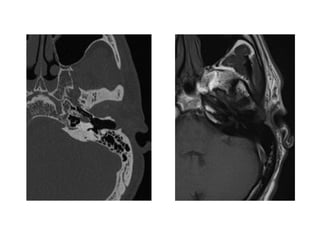

Axial contrast-enhanced CT image shows opacification of the right mastoid,

middle ear, and anterior petrous air cells.

There is cortical erosion along the posterior margin of the petrous apex (arrow).

Note the pneumatization of the left petrous apex.

Gadolinium-enhanced fat-suppressed T1-weighted MR image shows diffuse

enhancement throughout the right mastoid and middle ear, anterior petrous

apex, and clivus.

There is also a focal rim-enhancing fluid collection in the anterior petrous apex

(arrowhead), a finding consistent with an abscess.